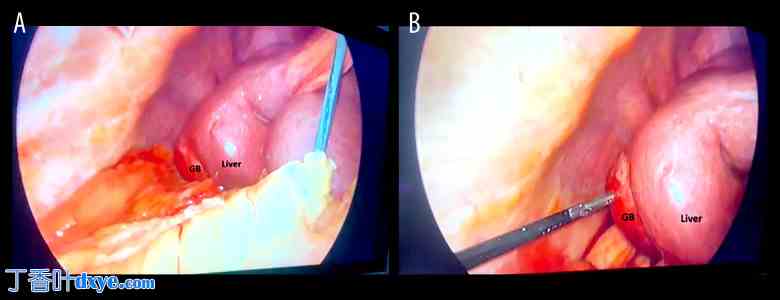

为排除任何异常,患者进行了腹部静脉造影CT检查。CT显示胆囊位于肝脏右背侧,胆囊颈部嵌顿有结石(图1)。肝右叶严重发育不全,左叶代偿性肥大。动脉视图可见肝右动脉起源于肝门,向下延伸,末端闭锁,可能通向萎缩的肝右叶(图2)。静脉视图可见肝右静脉(图3)。

图 2.

增强 CT,动脉期。(A) 箭头指示腹腔干的主要分支:肝总动脉(红色箭头)和脾动脉(蓝色箭头);(B) 箭头指示肝总动脉的分支:肝左动脉(红色箭头)和肝右动脉(蓝色箭头)。